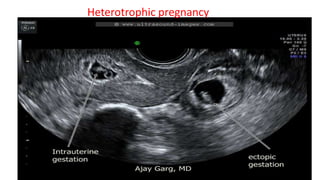

This document discusses the evaluation of right lower abdominal pain and lists appendicitis as a key cause. It notes that other potential causes include hemorrhagic cysts, heterotrophic pregnancy, salpingitis with pyosalpinx, funiculitis, and torsion of an undescended testis. The document was presented by Dr. A.S.M. Sufian of Cumilla Medical College Hospital and thanks the audience for their patience and listening.